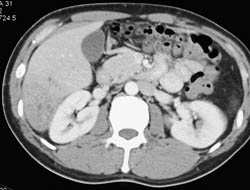

Liver Abscess